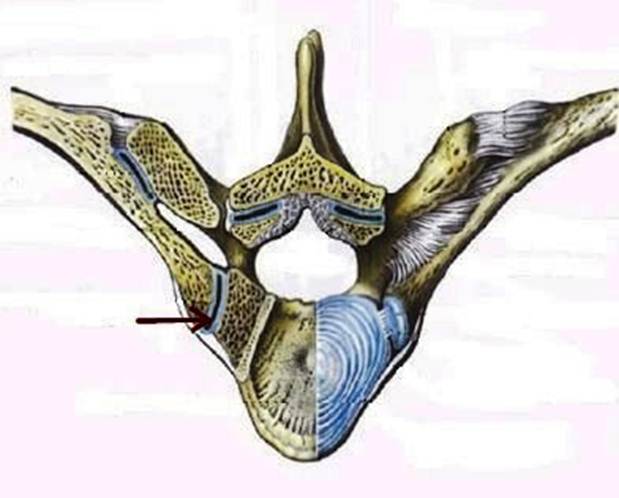

S: Стрелка указывает на art. Costotransversaria

S: Стрелка указывает на art. Capitis costae

S: Стрелками выделен art…